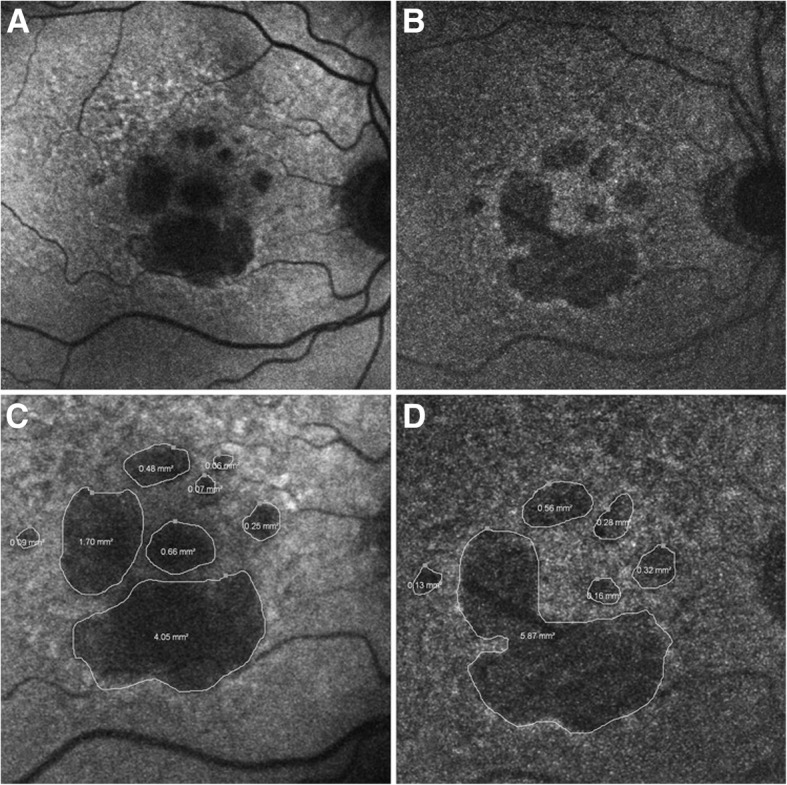

NIR-AF was performed to detect melanin in patients and study diseases such as AMD [45, 48, 50–52] (see Fig.2), idiopathic choroidal neovascularization [53], chloroquine retinopathy [54], various inherited retinal diseases [55], ABCA4-associated retinal degenerations [56–58], retinitis pigmentosa [9, 59, 60], Usher syndromes [49, 61], Best vitelliform macular dystrophy [62], diabetic macular edema [63], central serous chorioretinopathy [64, 65], and torpedo maculopathy [66]. NIR-AF has multiple advantages as a melanin imaging technique: it offers a large imaging field-of-view, does not require exogenous contrast agents, is safe and comfortable for the patient, can be performed using commercially available equipment, and produces images that are easy to interpret by researchers and clinicians. However, NIR-AF does not have the axial resolution to produce three-dimensional images of the melanin distribution and it is likely that melanin from the RPE and choroid are both contributing to the NIR-AF signal. Additionally, the interpretation of the NIR-AF is mostly qualitative since the fluorescence intensity is highly dependent on imaging conditions. The NIR-AF signal can thus be quantified within one eye [45, 63] but it has been difficult to directly correlate the NIR-AF signal to an absolute measure of melanin concentration that would be valid across multiple eyes. However, quantitative autofluorescence has been performed in the eye to quantify lipofuscin in short-wavelength autofluorescence (SW-AF) images with the use of an internal fluorescent reference [67–69], which is encouraging for future quantitative autofluorescence measurements of melanin in the eye. In conclusion NIR-AF is easily performed using commercially available instruments and has been used to study multiple human diseases. However, RPE melanin cannot be separated from choroidal melanin and further research is needed to obtain quantitative NIR-AF results.

Fig. 2.

Geographic atrophy (GA) in the foveal region due to age-related macular degeneration (AMD) imaged with (a) short-wavelength autofluorescence (SW-AF) to detect lipofuscin, and (b) near-infrared autofluorescence (NIR-AF) to detect melanin. Areas of hypo-fluorescence (c, d) corresponds to GA. Larger areas of hypo-fluorescence are detected with (c) SW-AF compared to (d) NIR-AF, which may indicate that SW-AF overestimates areas affected by GA in the fovea. Reproduced from [50] with permission from BMJ Publishing Group Ltd.